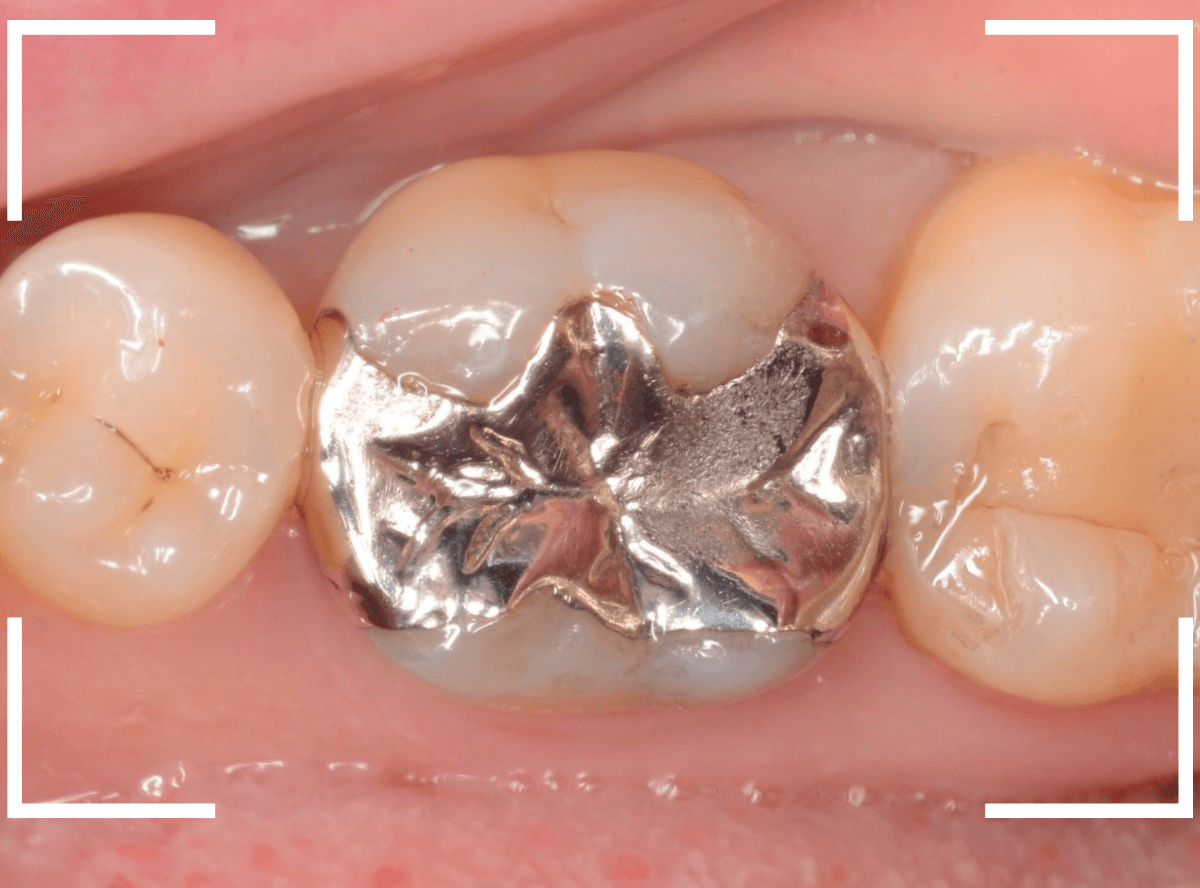

今回は、上の奥歯の銀歯(メタル・クラウン)の中で虫歯になってしまった方です。

通常は、さし歯の中が虫歯になってしまうと、レントゲンにも写らず見つけづらいのですが・・・。

歯を裏側から見たところです。

幸い、見える部分に虫歯が

さし歯と歯肉の間に虫歯ができているのがわかります。

歯の奥まで虫歯が進んでいるのか、浅い虫歯ですんでいるのかは治療をしながら調べていく必要があります。